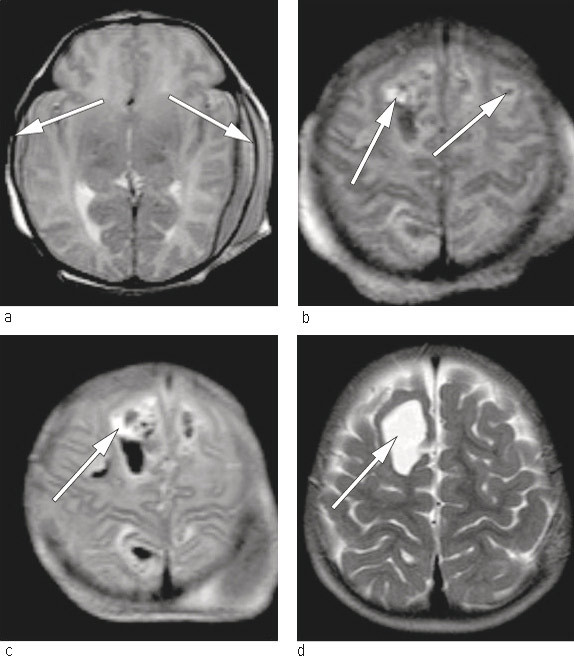

To friske, ubeslektede foreldre fikk sitt første barn etter et ukomplisert svangerskap. Fødselen skjedde ved svangerskapslengde 39 uker og to dager. Barnet ble født etter akutt keisersnitt pga. occiput posterior, langtrukket fødselsforløp og risvekkelse. Barnet var slapt og blekt ved fødselen, veide 2 740 g og fikk apgarskår 2, 6, 7 etter henholdsvis ett, fem og ti minutter. På grunn av respiratorisk besvær ble hun ventilert ved hjelp av maske og bag de første tre minuttene, deretter med Neopuff (maske-CPAP) i 15 minutter. Det ble observert multiple petekkiale hudblødninger samt hematomforandringer over caput like etter fødselen. Hematologiske prøver viste alvorlig trombocytopeni – 9 · 109 celler/l (145 – 390 · 109 celler/l). Det ble gitt bestrålt trombocyttkonsentrat fra fire tilfeldige givere (15 ml/kg), intravenøs injeksjon av polyklonalt immunglobulin (IVIg) på 0,8 g/kg samt K-vitamin peroralt. Cerebral ultralyd viste parenkymatøs blødning medialt i parietalcortex bilateralt. For nærmere kartlegging ble det utført MR caput, som avdekket bilaterale kortikale og epidurale blødninger (fig 1). Disse ble tolket som ferske. Nevrokirurg anbefalte videre observasjon og konservativ behandling.

Etter utskrivning ble barnet fulgt med blodprøver, først hver måned og deretter annenhver måned i et halvt år. Trombocyttverdiene lå hele tiden innenfor normalområdet (326 – 402 · 109 celler/l). MR caput ble gjentatt ved én og 15 måneders alder (fig 1). Barnet har senere vist normal psykomotorisk utvikling og er i dag en frisk femåring.

For barn nummer én var fødselsforløpet frem til operativ forløsning langtrukkent. Den intrakraniale blødningen var fersk på fødselstidspunktet (fig 1). Man kan stille spørsmålet om hvorvidt dette kunne ha vært unngått dersom man hadde kjent til morens trombocyttype og antistoffnivå i svangerskapet og utført keisersnitt 2 – 3 uker før termin med forlikelige trombocytter i beredskap til barnet.